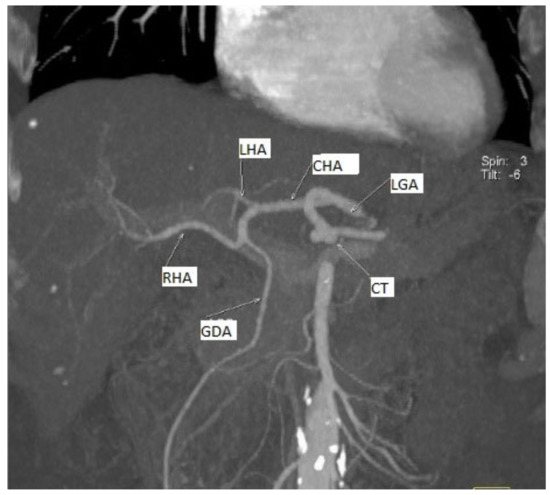

- A gastro–splenic trunk associated with the origin of the RCHA from the LGA in 1.31% of cases (one case) (Figure 2).

Figure 2. MDCT angiography, coronal view. 3D reconstruction, for a better view of the described arteries we used gantry tilt/spin (degrees -6/3). Replaced common hepatic artery originating from the left gastric artery. Female patient, 66 years old, with a diagnosis of PAD.